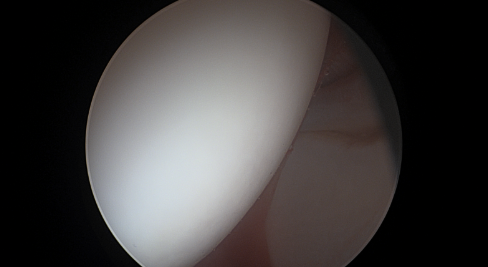

Η ακρίβεια στην οστεοπλαστική στη μορφολογία cam, αποτελεί ένα φλέγον ζήτημα τα τελευταία χρόνια.  Έχουν προταθεί διάφοροι τρόποι για ακριβή αφαίρεση οστού κατά τη διαδικασία αυτή, και υπάρχουν νέες τεχνολογικές και πολλά υποσχόμενες τεχνικές που εφαρμόζονται σε πολλά κέντρα. Ένας προτεινόμενος τρόπος για αυξημένη ακρίβεια είναι το Computer Navigation, το οποίο χρησιμοποιείται σε πολλά κέντρα του εξωτερικού.

Σε μία νέα μελέτη έγινε προσπάθεια να εκτιμηθούν τα αποτελέσματα της χρήσης ενός συστήματος Computer Navigation σε ασθενείς με μορφολογία cam ή συνδυασμό μορφολογίας cam και pincer, και να συγκριθούν τα αποτελέσματα με τεχνική free hand (τεχνική χωρίς ηλεκτρονική βοήθεια).

Η μελέτη αυτή ήταν αναδρομική και συμπεριλάμβανε ασθενείς που αντιμετωπίστηκαν μεταξύ των ετών 2020 και 2014, και υπεβλήθησαν σε πρωτοπαθή αρθροσκόπηση ισχίου για cam ή μικτή μορφολογία.  Eίχαν διαθέσιμη προεγχειρητική και μετεγχειρητική αξονική τομογραφία του ισχίου και είχαν ελάχιστη παρακολούθηση 12 ετών.  Χωρίστηκαν σε δύο κατηγορίες και η μία υποβλήθηκε σε χρήση συστήματος Computer Navigation, ενώ η δεύτερη σε συμβατική, χωρίς βοήθημα τεχνική. Η εκτίμηση του προχειρητικού πλάνου εκτιμήθηκε με τη διενέργεια μετεγχειρητικής τρισδιάστατης αξονικής τομογραφίας σε κάμψη 90°, 70° και 45°.  Για την εκτίμηση του κλινικού αποτελέσματος χρησιμοποιήθηκαν οι κλίμακες αξιολόγησης Harris Hip Score και Non-Arthritic Hip Score.

Συνολικά συμπεριελήφθησαν 55 ισχία (25 στην ομάδα της navigation και 30 στη συμβατική τεχνική).  Ο μέσος χρόνος παρακολούθησης ήταν 14,7 ± 4,4 μήνες στην ομάδα navigation και 31,3 ± 11,2 μήνες στην ομάδα της συμβατικής τεχνικής.  Στον ένα χρόνο το Non-Arthritic Hip Score είχε στατιστικά σημαντική διαφορά στην ομάδα του navigation, όμως η κλίμακα αξιολόγησης Harris Hip Score, το ποσοστό επανεγχείρησης και μετατροπής σε ολική αρθροπλαστική ισχίου ήταν το ίδιο και για τις δύο ομάδες.

Οι συγγραφείς συμπέραναν ότι το computer navigation μπορεί να βελτιώσει την ακρίβεια στην αφαίρεση οστού και να οδηγήσει σε καλύτερα μεσοπρόθεσμα αποτελέσματα όσον αφορά το Non-Arthritic Hip Score, ωστόσο τα πλεονεκτήματά του είναι περιορισμένα όσον αφορά τα αποτελέσματα του Harris Hip Score, το ποσοστό επανάληψης της αρθροσκόπησης και μετατροπής σε ολική αρθροπλαστική ισχίου.